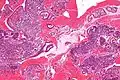

Micrographie montrant la condensation stromale de l'endomètre, observée lors des menstruations.